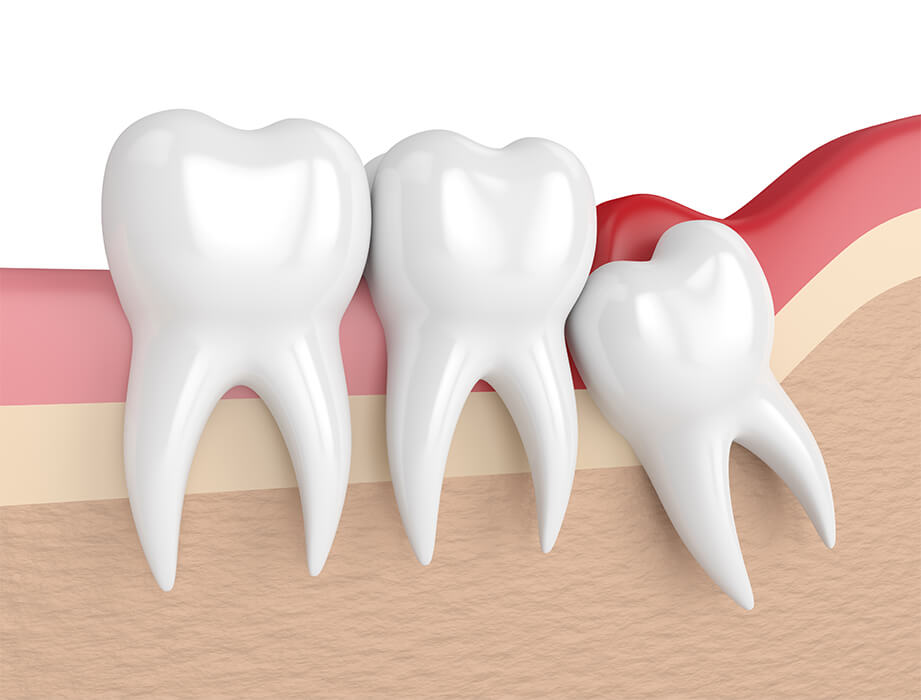

Les dents de sagesse sont les troisièmes molaires, les dernières sur l’arcade dentaire, qui, au fil de l’évolution de l’alimentation, ont perdu de leur utilité chez l’humain. Elles font généralement leur éruption entre 18 et 25 ans mais peuvent parfois arriver dans la cavité buccale bien plus tard.